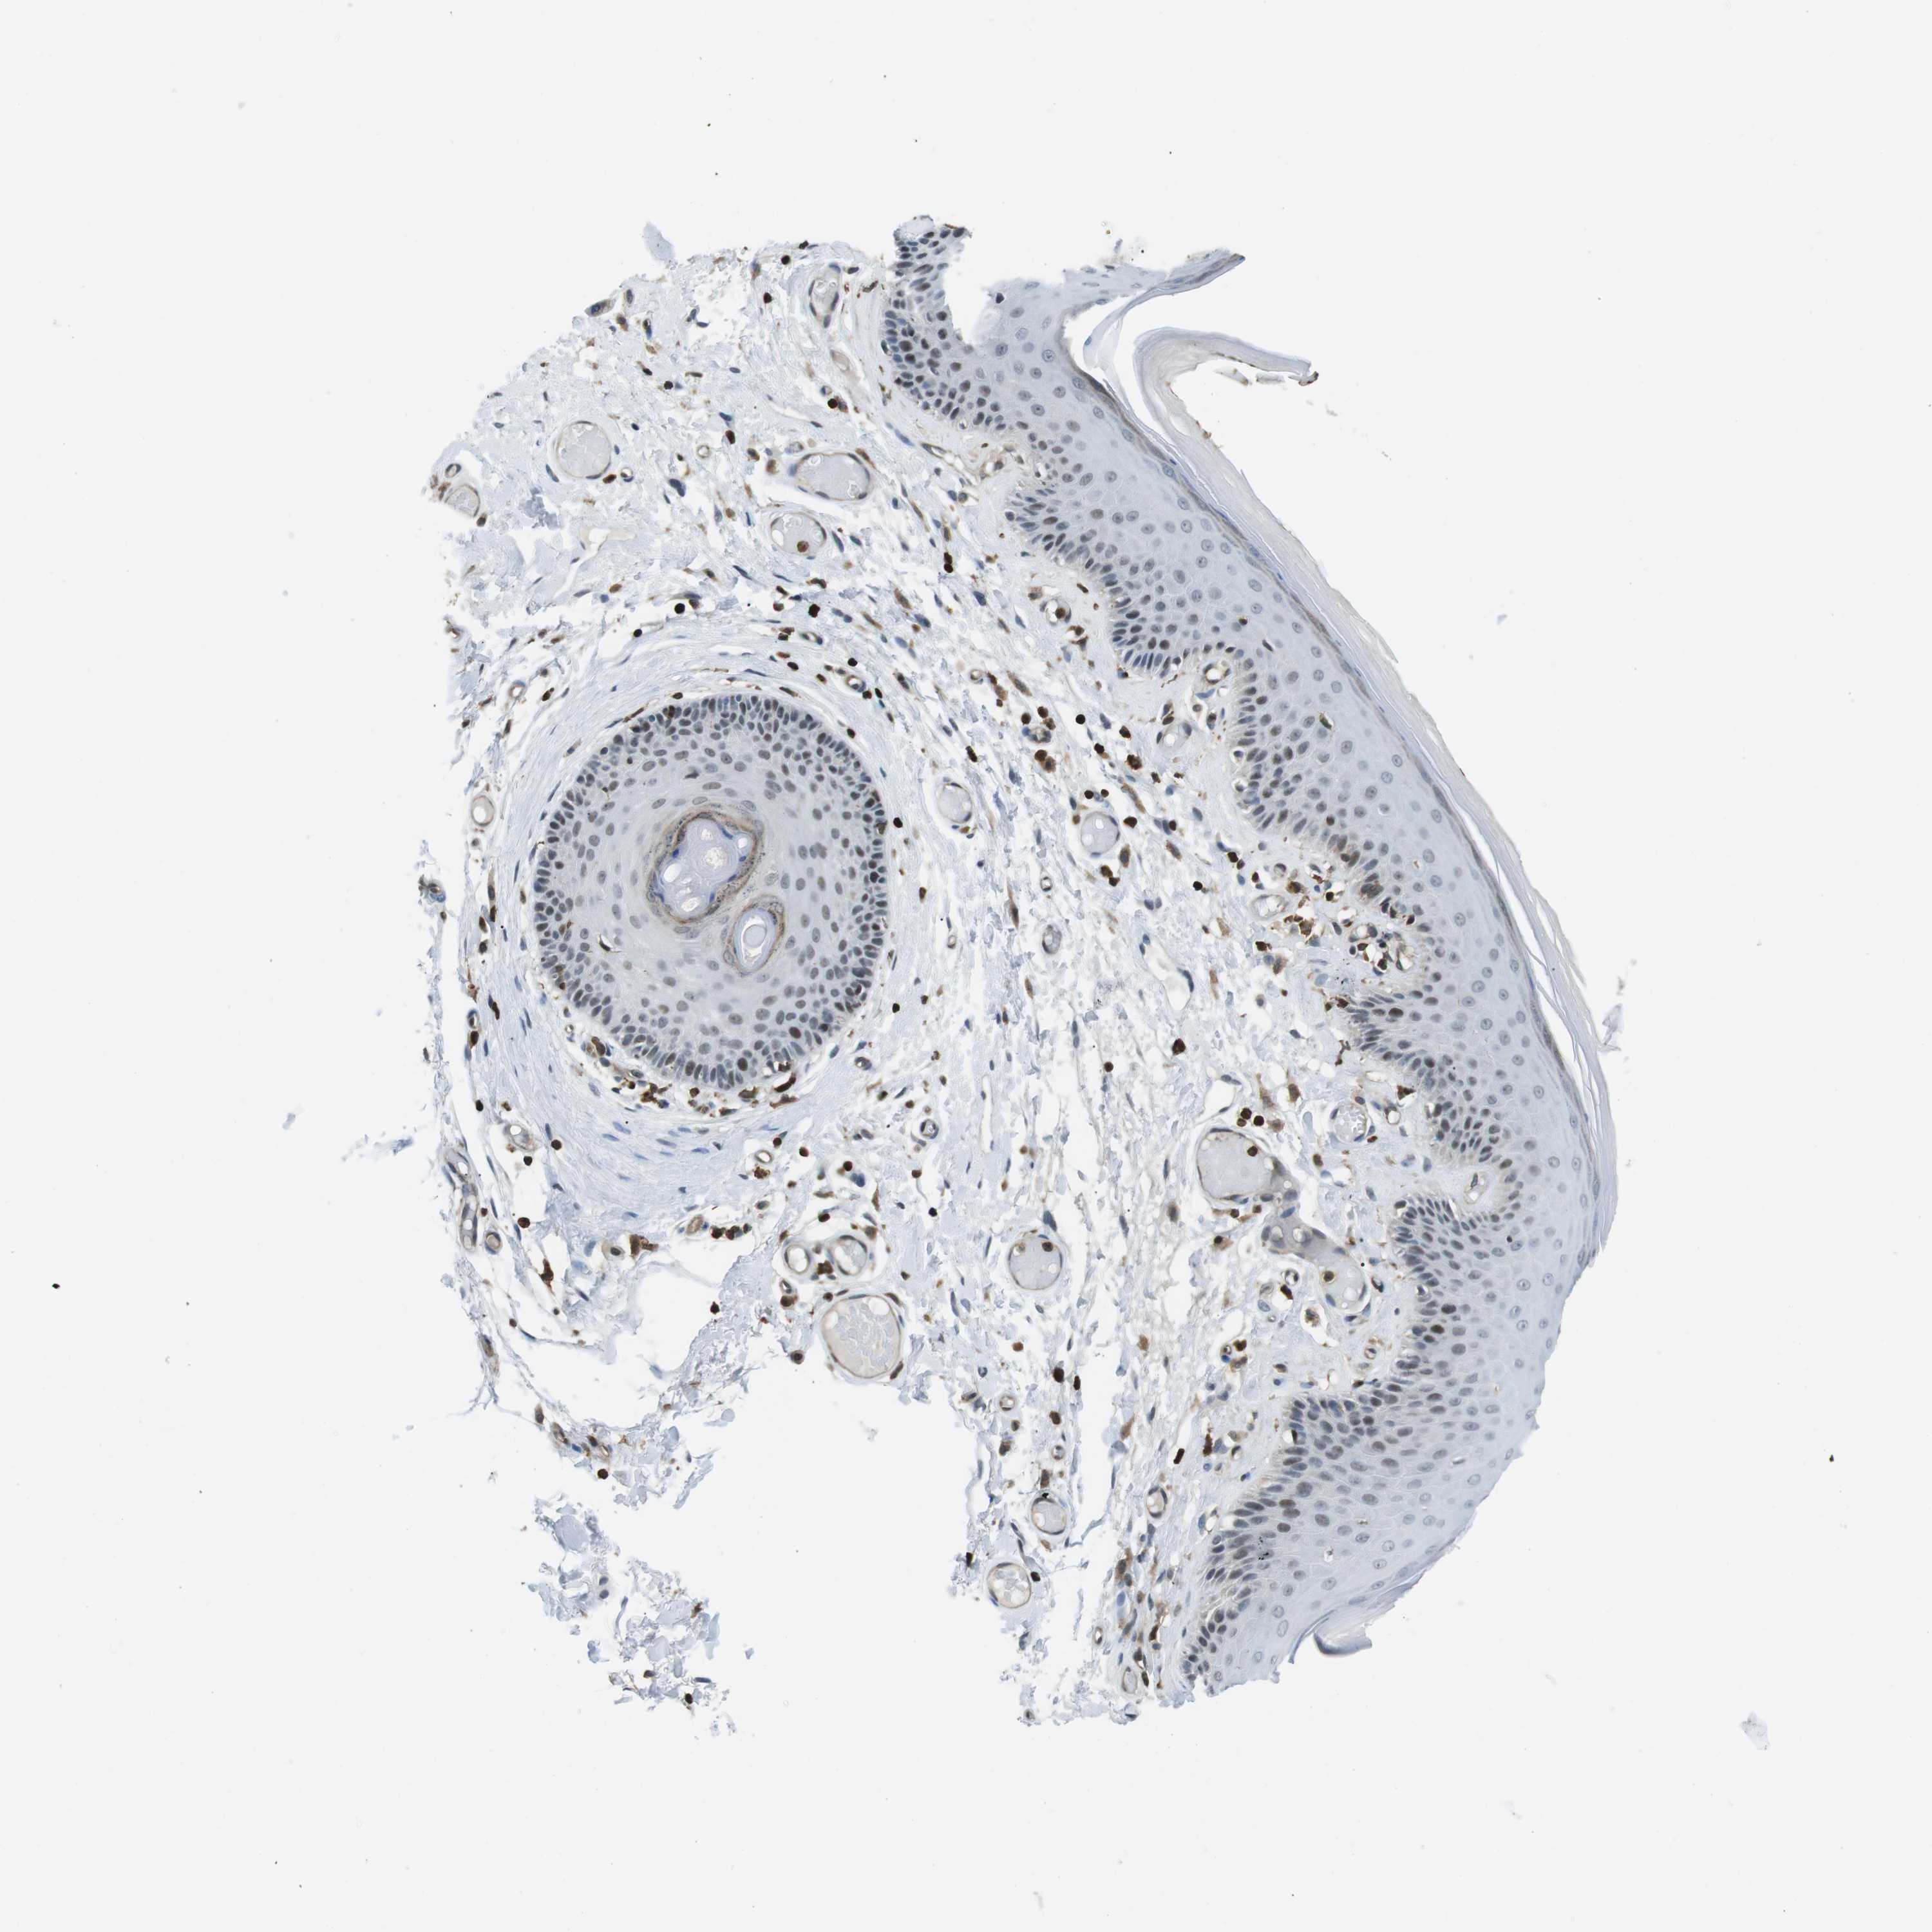

SKIN 1 - Antibody stainingi

Antibody staining in the annotated cell types in the current human tissue is reported as not detected, low, medium, or high, based on conventional immunohistochemistry profiling in selected tissues. This score is based on the combination of the staining intensity and fraction of stained cells. Each image is clickable and will lead to virtual microscopy that enables deeper exploration of all samples and also displays staining intensity scores, fraction scores and subcellular localization as well as patient and tissue information for each sample.

Antibody HPA015083Antibody CAB020840

Langerhans Not detectedNot detected

Fibroblasts LowLow

Keratinocytes Not detectedLow

Melanocytes MediumNot detected